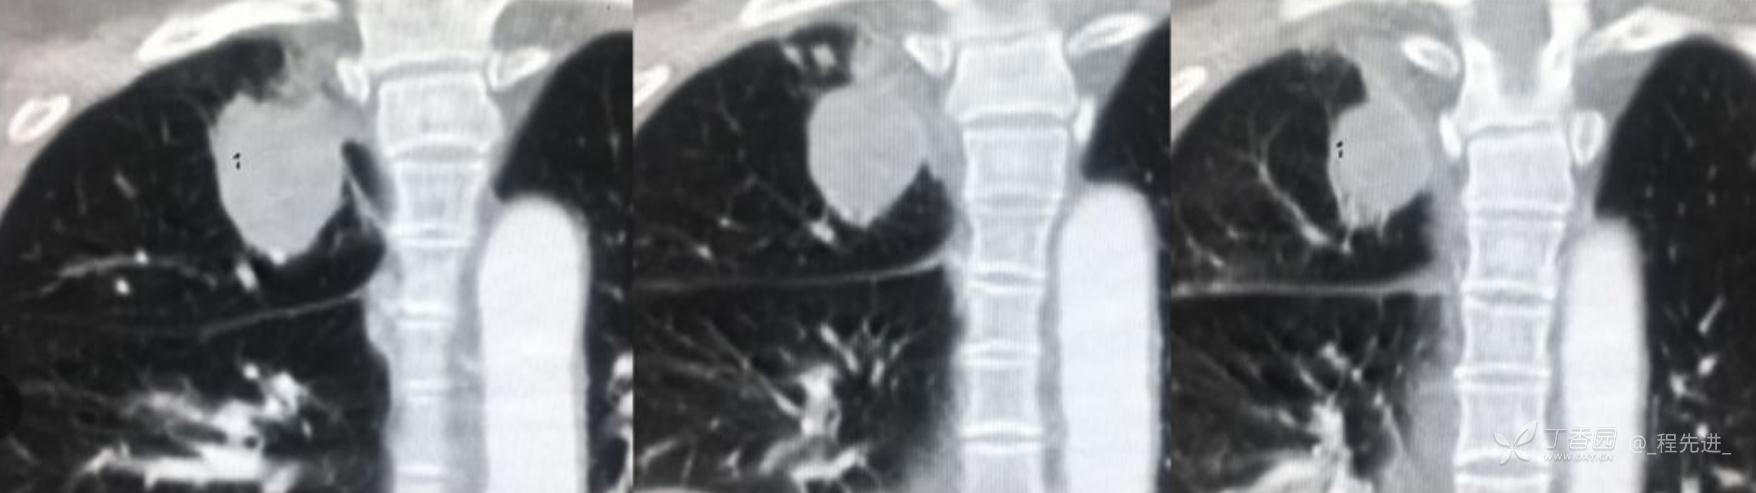

简要病史:乏力、纳差20余天,皮肤巩膜黄染半月偶有咳嗽,咳白痰,全身皮肤巩膜黄染。无咯血,无明显胸闷、胸痛,无明显气促,无发热及盗汗。精神欠佳,纳差,睡眠一般,二便正常